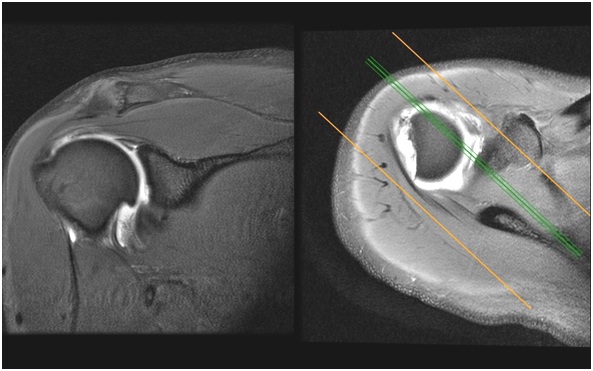

Artroresonancia de hombro